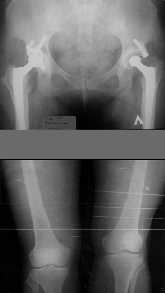

1. Иллюстрации - во вложении.

Два бедра после эндопротезирования.

Авторы операции долго думали почему больная хромает.

Сдклали снимок - одна нога короче почти на 3 см.

Здоровый человек и то будет хромать.

2. Другой пример - дефект после инфицирования коленного эндопротеза.

Предполагалось, что величина дефекта 11-12 см. Так получается, если

сделать снимок только области коленных суставов. Определить

укорочение сложно, так как нога просто болтатется.

Сделали снимок "от и до" - величина дефекта 17 см.

Правда эта иллюстарция сделана на цифровом рентгеновском аппарате.

Больной стоит, а трубка передвигается сверху вних, последовательно

выполняя рентгенограммы. В данном случае - 4 штуки.